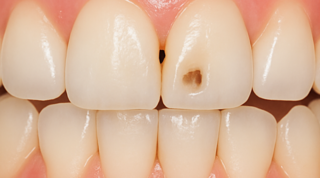

В стоматологической клинике "5 Принципов" в Симферополе мы гордимся тем, что каждый пациент получает индивидуальный подход и безупречный результат в области эндодонтического лечения под микроскопом. Наши специалисты применяют современные цифровые технологии, микропроцессорные и нейромодуляционные инструменты, что позволяет достичь максимальной точности и минимального дискомфорта. В портфолио клиники — широкий спектр кейсов: от первичной диагностики пульпита до сложной ретенированной резорбции и повторной эндодонтии. Мы беремся за зубы любых степеней сложности: от моляра до резцов, используя щадящие концевые инструменты и безболезненные методы постоянной анестезии. Все процедуры проходят под увеличением, что обеспечивает точное удаление инфицированной ткани и сохранение естественной анатомии зуба.Особое внимание мы уделяем постпроцедурному наблюдению: контроль за герметичностью заполнения корневых каналов, профилактические рекомендации и возможная корректировка плана лечения при необходимости. В "5 Принципах" мы разумно сочетаем комфорт, эстетическую привлекательность и долгосрочную функциональность. Результат — здоровые зубы, уверенная улыбка и спокойствие наших пациентов в Симферополе. Запишитесь на консультацию и убедитесь сами в нашем подходе к качественному эндодонтическому лечению.